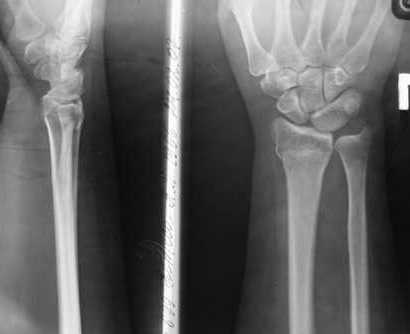

Уважаемые коллеги, обращаюсь к вашему опыту. Обратилась женщина 45лет, профессия - швея, травма 24.02.07 вколоченный перелом правого луча (см Ргр )

Лечилась: гипсовая иммобилизация 4 нед, препараты кальция. В реабилитационном периоде получала ЛФК, изотерапию, медикаментозные болкады. На данный момент женщину беспокоят слабокупирующиеся боли плечо-локоть-кисть по локтевой поверхности больше, ограничение движений в л\з суставе и мелких суставах кисти (см приложения: общий вид, объем движений,

на Ргр нарастают явления остеопороза, не смотря на прием препаратов кальция.

Видимо там был оскольчатый перелом луча и шиловидного отростка

локтевой кости.

В гипсовом повязке наблюдалось вторичное смещение костных отломков по длине (при передне-заднем рентгенограмме), и при боковй проекции видно смещение отломка в дорсальном направлении и таким

образом последный дает компрессию нервов в лучезапястном канале (типа синд. Зудека)